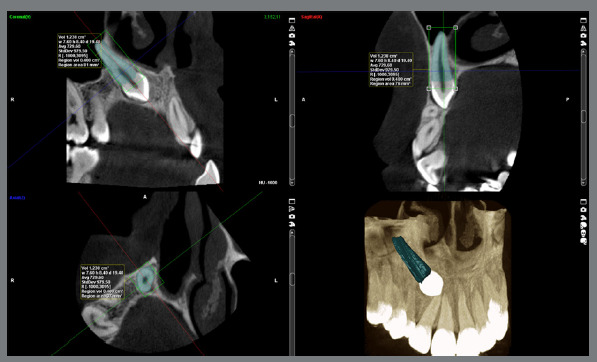

Methods: This cross-sectional study was performed on cone-beam computed tomography (CBCT) scans of 100 patients (49 females and 51 males) with unilateral maxillary canine impaction. The images were loaded in Planmeca Romexis Viewer, and root layers between the cementoenamel junction and apex were reconstructed at 600-µm intervals. At each layer, the root boundary was marked, and finally, the root volume was calculated by multiplying the layers' area by the thickness of 600 µm. The root size of canines and lateral incisors was compared between the impaction and normal eruption sides.

Abstract Image